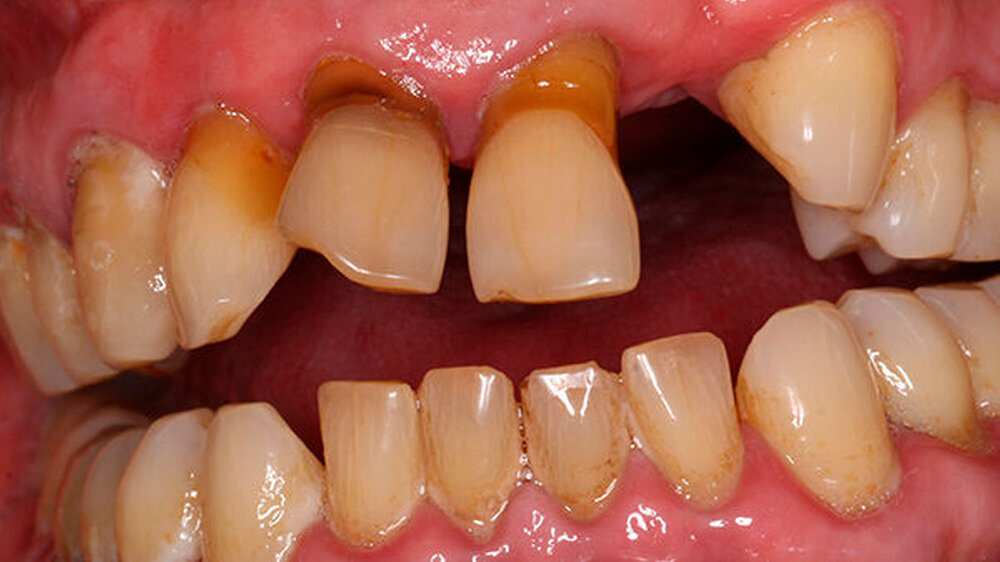

Ein 80 Jahre alter Patient stellt sich im September 2016 in der Poliklinik mit der Bitte um festsitzende Versorgung der Frontzahnlücke in Regio 22 vor (Abbildungen 1 und 2) Der Zahn 22 musste vor etwa einem Jahr parodontal bedingt extrahiert werden. Seitdem war diese Lücke durch einen Interimsersatz versorgt. Nach klinischer und röntgenologischer Befundung stellt sich schnell die Problematik dar, die im Rahmen der Versorgung dieser Frontzahnlücke auftreten wird.

Die Versorgung der Frontzahnlücke in Regio 22 wird intensiv mit dem Patienten diskutiert. Aufgrund des absoluten Mangels an ortsständigem Knochen, des hohen Patientenalters sowie der eher mäßigen Mundhygiene scheidet eine Implantation mit Knochenaugmentation aus. Hinzu tritt die starke, vor allem im Frontzahngebiet ausgeprägte Parodontitis. Ein langfristiger Erhalt des endodontisch versorgten 11 sowie des stark parodontal kompromittierten 21 erscheint unrealistisch.

Für eine konventionelle brückenprothetische Versorgung scheiden die Schneidezähne ebenfalls aus: Zum langfristig prognostisch sicheren Ersatz des 22 wären Extraktionen und mehrere Substanz-opfernde Präparationen unausweichlich. Aufgrund des hohen Patientenalters und des Ausscheidens klassischer prothetischer Rehabilitationsmaßnahmen wird die Frontzahnlücke mit einer Adhäsivbrücke aus Metallkeramik versorgt (Abbildungen 3 und 4).